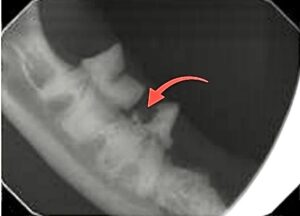

Dental x-rays confirmed the diagnosis of tooth resorption, and this step is absolutely critical. Feline resorptive lesions typically begin below the gumline, where we cannot see them with the naked eye. Even teeth that look relatively normal on the surface can be severely affected underneath. Without x-rays, we are only seeing the tip of the iceberg.